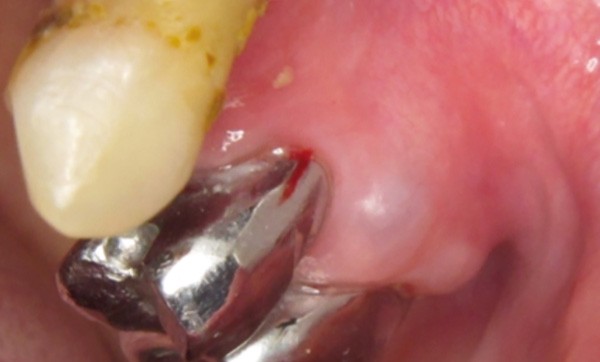

Examen clinique. Il révélait un nodule translucide, légèrement bleuté, de 5 mm de diamètre, situé sur et sous la papille gingivale bordant les 24 et 25. Le nodule était très discrètement dépressible à la palpation avec le dos de la sonde.

Examen paraclinique. La lésion a été excisée et l’examen histopathologique de la pièce d’exérèse a été réalisé. L’examen macroscopique révélait une poche remplie d’un liquide clair. L’examen microscopique a révélé que la tumeur était limitée par un épithélium malpighien pluristratifié constitué de 2 à 3 couches de cellules.